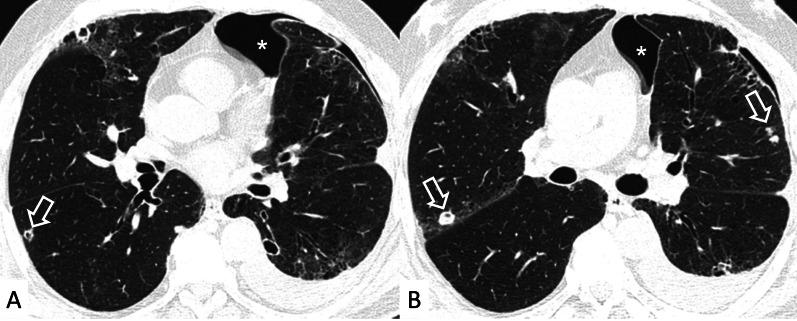

Connective tissue diseases (CTDs) include a spectrum of disorders that affect the connective tissue of the human body; they include autoimmune disorders characterized by immune-mediated chronic inflammation and the development of fibrosis. Lung involvement can be misdiagnosed, since pulmonary alterations preceded osteo-articular manifestations only in 20% of cases and they have no clear clinical findings in the early phases. All pulmonary structures may be interested: pulmonary interstitium, airways, pleura and respiratory muscles. Among these autoimmune disorders, rheumatoid arthritis (RA) is characterized by usual interstitial pneumonia (UIP), pulmonary nodules and airway disease with air-trapping, whereas non-specific interstitial pneumonia (NSIP), pulmonary hypertension and esophageal dilatation are frequently revealed in systemic sclerosis (SSc). NSIP and organizing pneumonia (OP) may be found in patients having polymyositis (PM) and dermatomyositis (DM); in some cases, perilobular consolidations and reverse halo-sign areas may be observed. Systemic lupus erythematosus (SLE) is characterized by serositis, acute lupus pneumonitis and alveolar hemorrhage. In the Sjögren syndrome (SS), the most frequent pattern encountered on HRCT images is represented by NSIP; UIP and lymphocytic interstitial pneumonia (LIP) are reported with a lower frequency. Finally, fibrotic NSIP may be the interstitial disease observed in patients having mixed connective tissue diseases (MCTD). This pictorial review therefore aims to provide clinical features and imaging findings associated with autoimmune CTDs, in order to help radiologists, pneumologists and rheumatologists in their diagnoses and management.

结缔组织病(CTDs)包括一系列影响人体结缔组织的疾病;它们包括以免疫介导的慢性炎症和纤维化发展为特征的自身免疫性疾病。肺部受累可能会被误诊,因为肺部改变仅在20%的病例中先于骨关节炎表现出现,且在早期阶段没有明确的临床发现。所有肺部结构都可能受累:肺间质、气道、胸膜和呼吸肌。在这些自身免疫性疾病中,类风湿关节炎(RA)的特征是普通型间质性肺炎(UIP)、肺结节和伴有空气潴留的气道疾病,而系统性硬化症(SSc)常表现为非特异性间质性肺炎(NSIP)、肺动脉高压和食管扩张。NSIP和机化性肺炎(OP)可见于多发性肌炎(PM)和皮肌炎(DM)患者;在某些情况下,可观察到小叶周围实变和反晕征区域。系统性红斑狼疮(SLE)的特征是浆膜炎、急性狼疮性肺炎和肺泡出血。在干燥综合征(SS)中,HRCT图像上最常见的表现是NSIP;UIP和淋巴细胞间质性肺炎(LIP)的报道频率较低。最后,纤维化NSIP可能是混合性结缔组织病(MCTD)患者中观察到的间质性疾病。因此,本图像综述旨在提供与自身免疫性CTDs相关的临床特征和影像学表现,以帮助放射科医生、呼吸科医生和风湿病科医生进行诊断和管理。